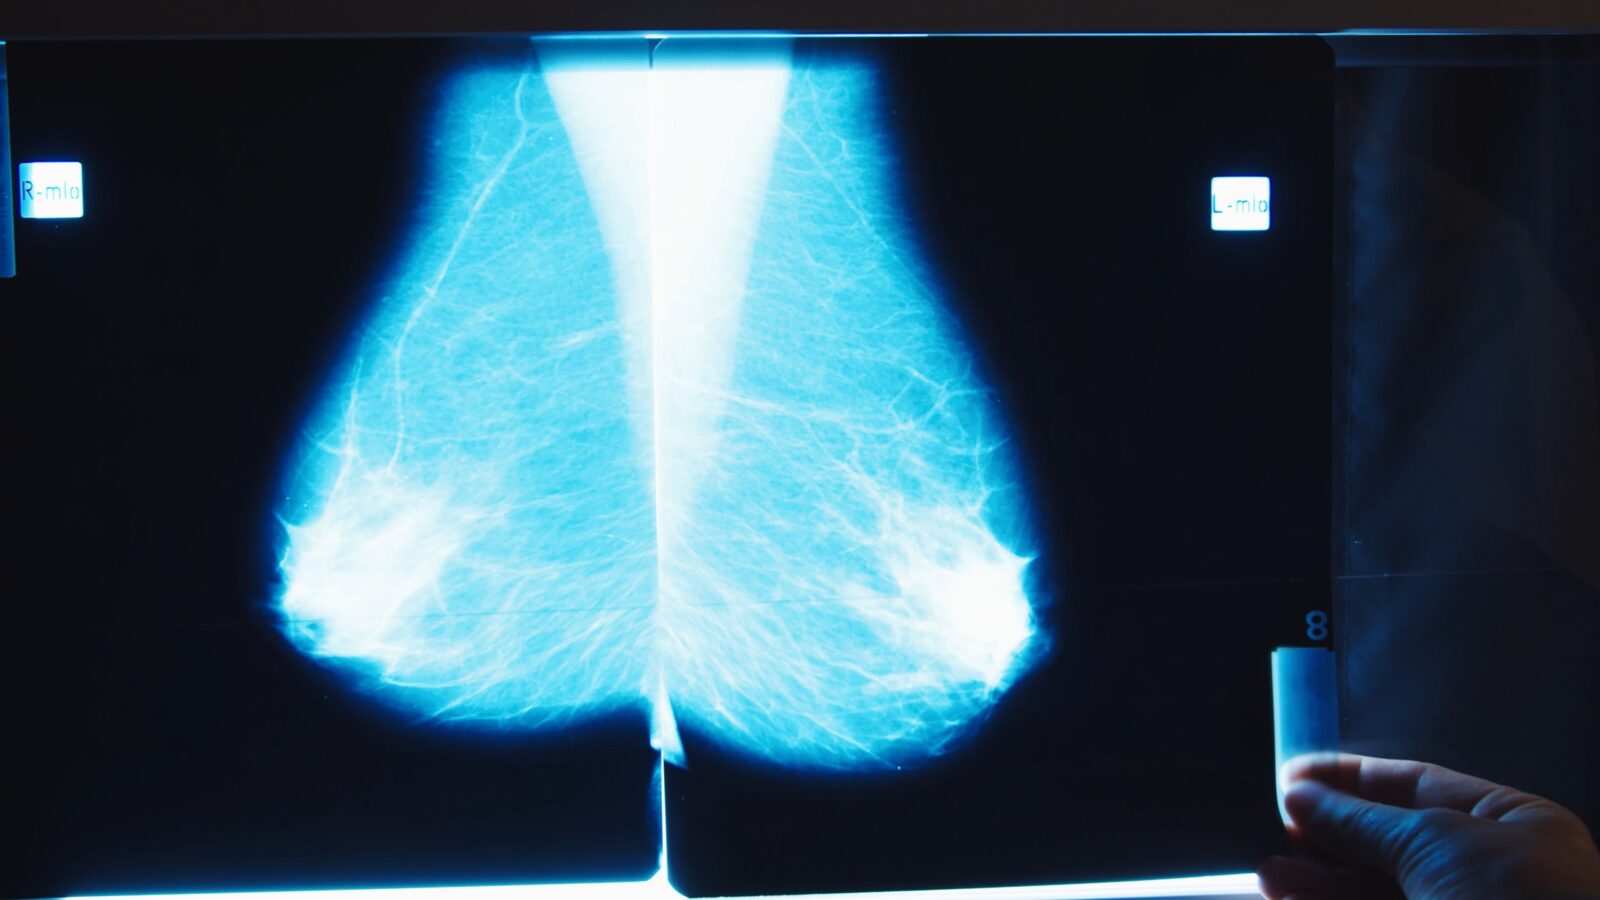

AI-based mammography is here. Human radiologists are skeptical

There's growing excitement around several FDA-approved AI tools that can analyze mammograms — with some research finding the algorithms do the job better than human radiologists. But the humans have some concerns, as STAT's Katie Palmer reports.

"We have to be very careful what we do with AI once it's out in the wild," said Etta Pisano, chief research officer at the American College of Radiology. And the tools are out there: RadNet, a company that owns more than 400 radiology practices, says it deploys its own algorithm in 600,000 mammograms each year. And it just acquired another company, iCAD, which claims 17% of U.S. radiology practices as customers. Still, those numbers pale in comparison to the 40 million mammograms analyzed by people every year. Read more from Katie on where expert skepticism comes from.